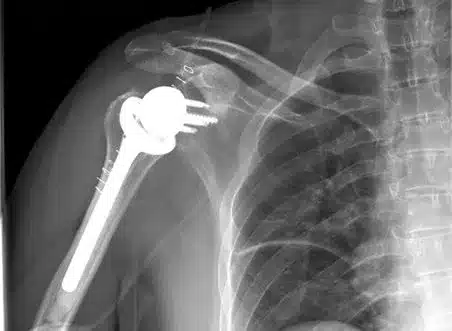

Especialista en Cirugía compleja de Hombro:

Cirugía Artroscópica y Prótesis

El Dr. Jorge Camacho Chacón es especialista en Cirugía Ortopédica y Traumatología, con dedicación preferente a la cirugía del hombro y de la cintura escapular. Con una amplia experiencia en el tratamiento de lesiones del manguito rotador, inestabilidades y artrosis, es uno de los referentes en Aragón en cirugía artroscópica y protésica del hombro.

Combina las técnicas quirúrgicas más avanzadas con un enfoque centrado en la preservación articular, buscando mantener la movilidad y funcionalidad del hombro y favorecer una recuperación rápida y segura.